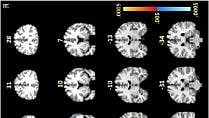

The imaging tests revealed unusual activity in the frontal lobe, an area of the brain responsible for cognitive tasks such as memory recall and concentration. Participants were asked to memorize and recall capital and lowercase letters, as well as the alphabetical order of multiple letters.

Notably, the researchers say, the images showed differences in their frontal lobe activity between the two groups in the white matter of the brain, which normally does not show up in fMRI scans, as this tissue operates with less blood flow than gray matter. White matter is crucial for moving information around the brain, acting like train tracks that help deliver information to the train depot, or gray matter.

“We saw certain areas in the frontal lobe under-activating and others that were over-activating, which was somewhat expected,” says Marvel, an associate professor of neurology. “However, we didn’t see this same white matter activity in the group without post-treatment Lyme.”

To confirm this finding, researchers used a second form of imaging called diffusion tensor imaging (DTI) on all 12 participants with Lyme and 12 of the 18 non-Lyme participants. DTI detects the direction of water movement within brain tissue. This unique approach corroborated their fMRI findings and revealed new findings: Water was diffusing, or leaking, along the patients’ axons — the extensions of neurons that carry electrical signals to other neurons — within the same white matter regions identified in the fMRI.